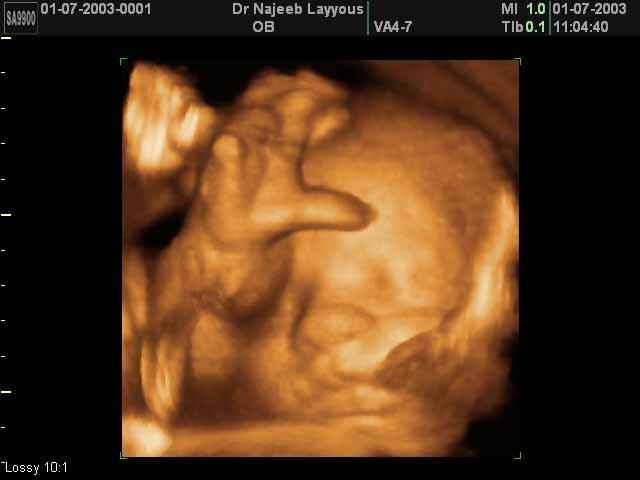

3D Fetal Face Ultrasound Scan Photos